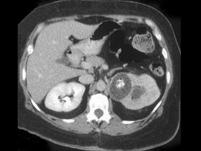

问题 女,42岁,左侧腰痛伴尿频、尿急、尿痛,尿白细胞(++),尿细菌培养为大肠杆菌,请根据所示图像,选择最可能诊断 ( )

选项 A、左侧肾转移瘤 B、左侧局限型黄色肉芽肿性肾盂肾炎 C、左侧肾结核 D、左侧肾脓肿 E、左侧肾癌

答案 B